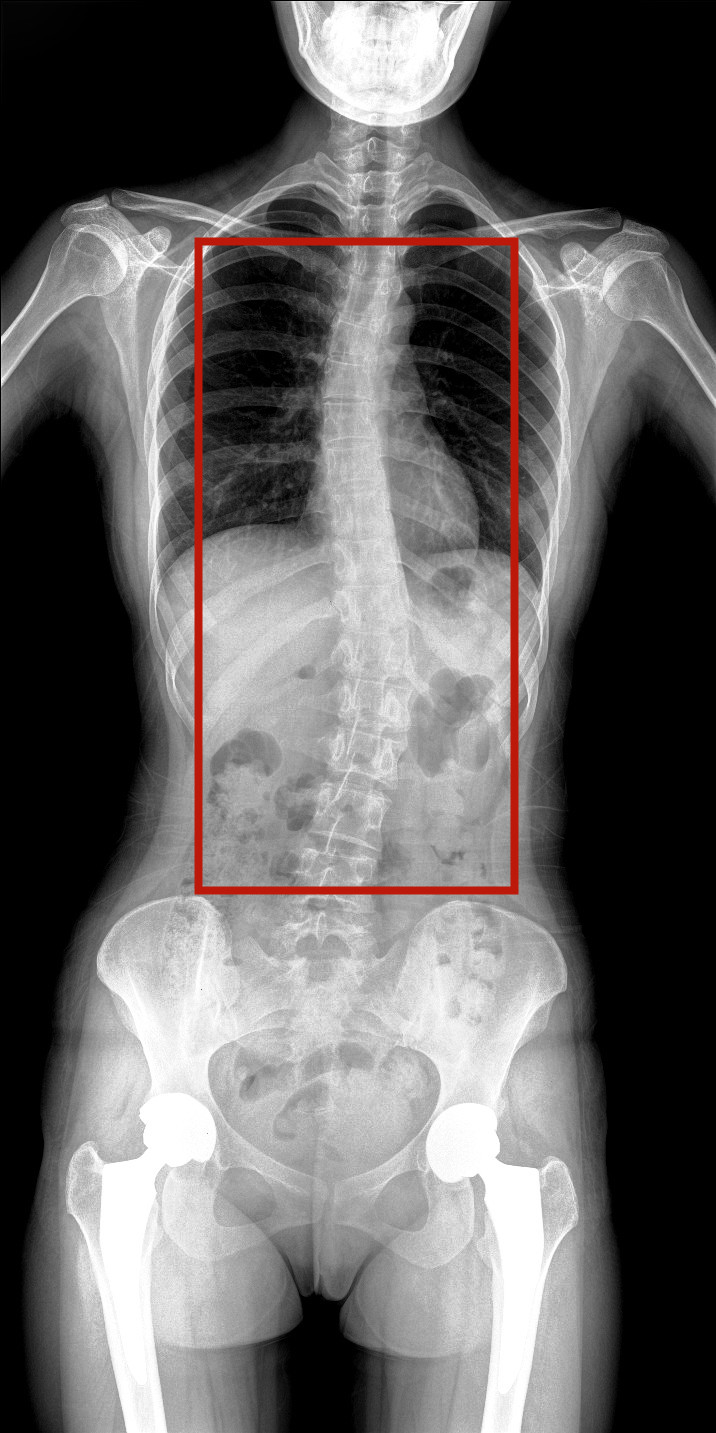

病情描述:患者,女,23岁,免疫系统畸变导致的脊柱侧弯

虚线框示患者脊柱侧弯明显

脊柱图像范围包含脊椎、双侧肩部及骨盆。片内颈椎、胸椎、腰椎、骶椎、双肩及骨盆重组影像结构清晰,对比度高,对位、对线好,接缘区无重叠、遗漏、缝隙。能够满足临床测量脊柱Cobb角及临床人体平衡线等指标的测量,整体上能对全脊柱进行观察诊断。